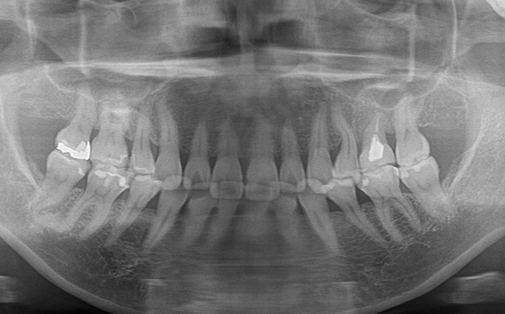

Before

After

左上の歯が折れています。折れた歯を抜き、親知らずの歯を移植しました。